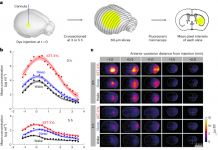

“코로나 후유증 세로토닌 고갈과 관련 있다”

신종 코로나바이러스 감염증 후유증 '롱 코로나'(Long COVID)가 세로토닌..